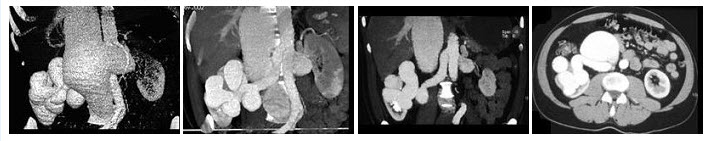

29、多项选择题

男,56岁,无痛性全程血尿1月,CT平扫及增强检查如图,下列说法正确的是()

A.右肾上极,肾脏局部隆起,平扫时其密度与肾相近,不易分辨其轮廓

B.增强扫描皮质期,病灶强化明显,但仍低于肾皮质的强化

C.增强扫描实质期,病灶强化迅速减退,可清楚的分辨其轮廓

D.右肾静脉及下腔静脉内未见充盈缺损影

E.考虑为右肾上极的肾癌